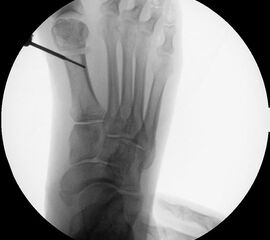

Instrumentarium für die minimalinvasive Vorfußkorrektur.

Abbildung 3

• Fräse für Minimalinvasive Fußchirurgie (Drehzahl: ca. 350 RPM, Drehmoment >50 N/cm).

• Shannon Fräser 20 mm, 2.0 mm Durchmesser.

• Shannon Fräser 12 mm. 2,0

• Bildverstärker.

• Beaver-Blade Messer.

• Mini-Raspatorium.

• Kanülierte Schrauben bis 60 mm Länge.

• Bohrmaschine.

• Kirschnerdrähte mit 1,2 mm (temporäre Fixation) und 2,4 mm (Reposition), special elevator.

• Verbandsmaterial für redressierenden postoperativen Verband (sterile Kompressen, Mullbinde, elastische Binde, Haftbinde, Pflasterstreifen).